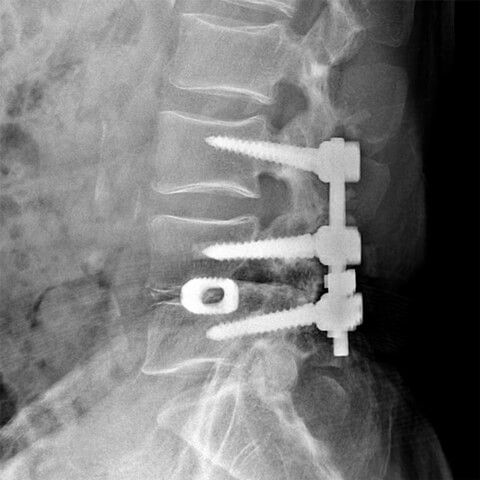

腰痛で手術をする場合、レーザー治療(PLDD法)やヘルニコア(椎間板内酵素注入療法)を除き、外科的手術が一般的です。椎間板ヘルニアであればヘルニア部分を切除することで神経への圧迫を減らし、脊柱管狭窄症やすべり症などの場合は脊椎(背骨)をボルトで固定する脊椎固定術を行います。

外科的手術で使用するボルト

• 長期入院や術後のリハビリが必要

• 早期社会復帰を望む方には対応が難しい

• 手術時間1時間~3時間

• メスで切開

脊椎手術の従来の手術方法は、全身麻酔をかけて皮膚をメスで切開し、ヘルニアや骨を切除したり骨をボルトで固定するという方法です。長期入院が必要であり、身体への負担が大きいため、ご高齢の方や大病をされ外科的手術ができない方にとっては難しい選択肢でした。当院は日帰りで、メスを使わず、0.8mmくらいの針を使い、椎間板だけをピンポイントに治療することができるため、比較的お身体への負担が少ない治療法です。